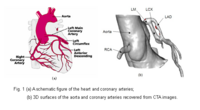

Blood Vessel SegmentationThe goal of this work is to develop blood vessel segmentation techniques for 3D MRI and CT data. The methods have been applied to coronary arteries and portal veins, with promising results. More... New: V.Mohan, G. Sundaramoorthi, A. Stillman and A. Tannenbaum. Vessel Segmentation with Automatic Centerline Extraction Using Tubular Tree Segmentation. CI2BM at MICCAI 2009, September 2009. |